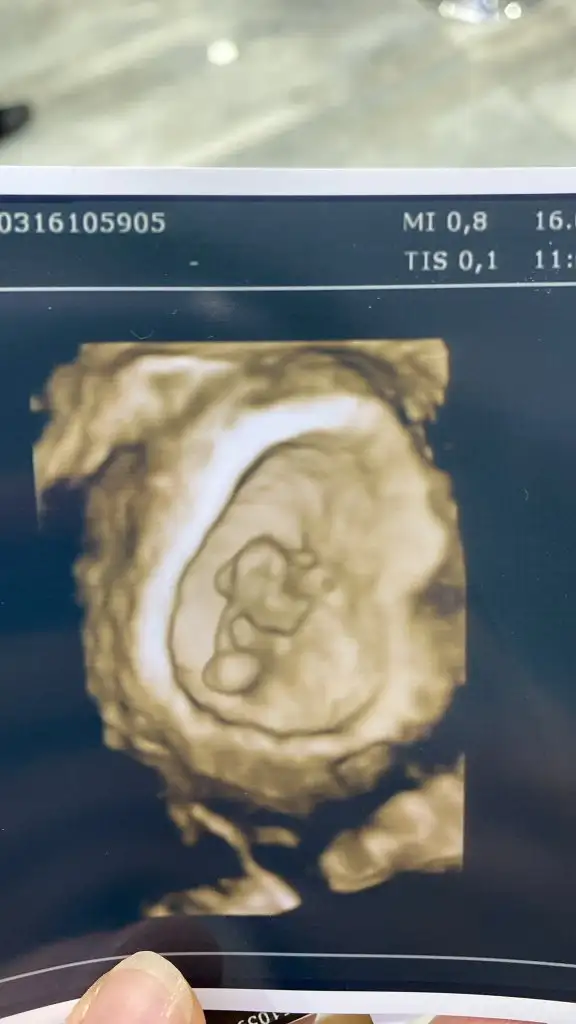

Çok rahat duyarsınız eli kolu bile belli oluyor 8. HaftadaArkadaşlar 6+3 Ken gittiğimde sadece kese var demişti şimdi 8+3 oldum bebek olusmusmudur kalp atışını duyabilir miyim yoksa beklemem mi lazim

Tamam kalp atışı gozukuyorsa sıkıntı yok. Küçük haftalarda dr lar kalp atisina onem veriyormus sadece boyutu onemli degil sonra gelişiyorlar Allahin izniyle. Ben özel bir sey yapmadim bol su içtim meyve sebze ve protein aldim her zamanki gibi. Ilac kullaniyorsan düzenli almaya çalış hic stres yapma canim❤Kalp atisi varmis 5+5de doktor var dedi ama dinletmedi bu haftada kucuk diye zorlamadi, haftaya dinletcekmis.yani 7+5de.umarim hizlica buyur.ben de yedigime ictigime daha cok dikkat etcem.sen ayrica bisey yapmismiydon canim

Başta cinsiyeti göremeyebiliriz suan zor dedi 3 boyutlu ultrasonla da baktı baya kız olma ihtimali yüksek dediben bel bağlamıyorum şuan ama ihtimal duymak bile cok iyi geldi

Aynen hatta ben aynayı gösterip simetrisine bakıyordum dhkgkfkdkdld doktor dalga geçer gibi benle dediAhhahahaha bende bu olayı yeni öğrendim zatenama dikkat ettim bazıları farklı yönlerde ultrasonda gözüküyor belki bi anlamı vardır dedim ama bilemiyorum